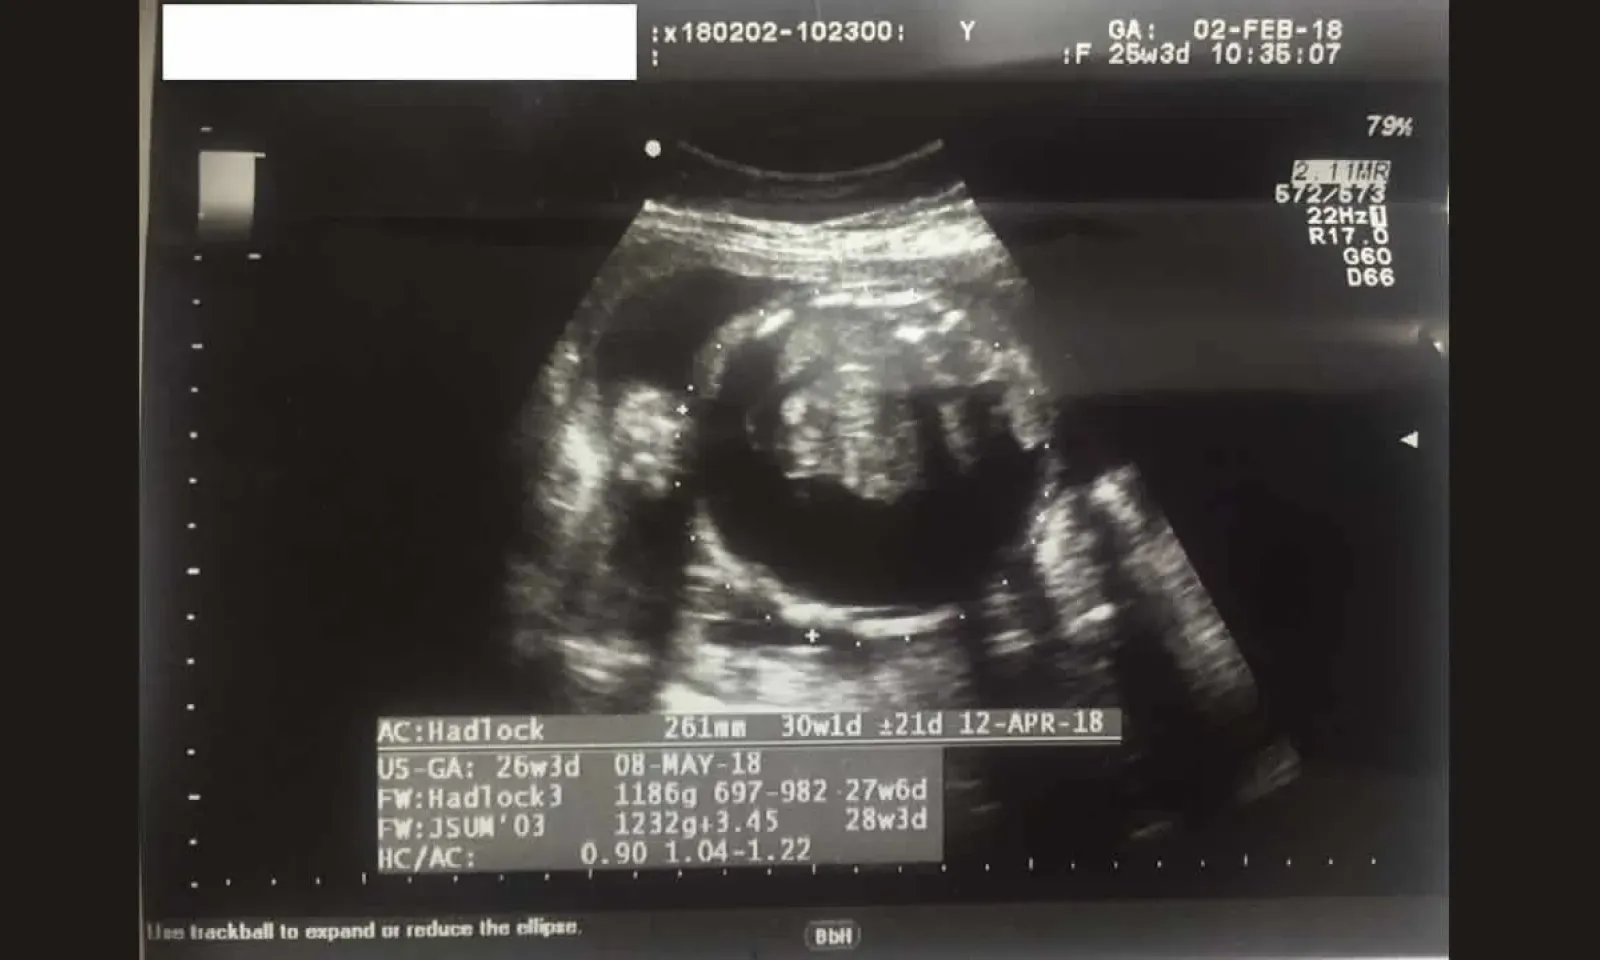

Le 22 décembre 2017, la femme en est à son quatrième mois de grossesse. Des boutons ‘anormaux’ sont apparus sur son ventre et elle ne se sent pas bien. Elle effectue sa première échographie et son médecin traitant à l’hôpital lui confirme que tout va bien pour le bébé et pour elle-même. Quelques jours après, vu qu’elle n’était toujours pas rassurée, elle décide de solliciter l’avis d’un autre gynécologue du privé. Après examen, la mauvaise nouvelle tombe : il y a de l’eau dans le ventre de son bébé.

Le médecin privé réfère Padmini à un confrère radiologue (toujours du privé) pour avoir un deuxième avis. « Effectivement, selon les résultats du deuxième examen, l’eau avait atteint 10 mm dans le ventre de mon bébé. Le gynécologue du privé m’a déclaré que la situation risquait d’empirer, puisque le volume d’eau pouvait augmenter et que c’est dangereux pour le bébé. Et d’ajouter que, normalement, à 16 semaines de grossesse, cette situation est visible lors de l’échographie », explique Padmini.